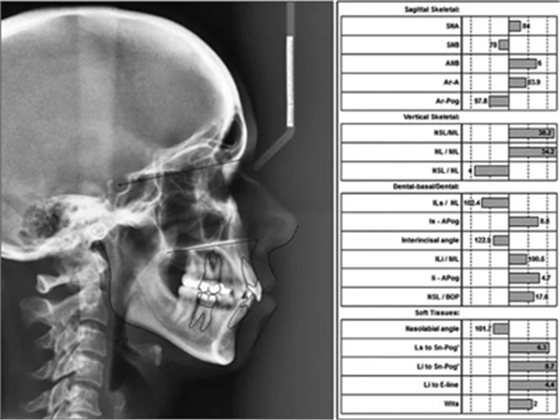

頭影測量分析,SNA角84°,ANB角6°,高角型,詳見下表。

患者側(cè)貌改善,下唇唇肌緊張消失,上下唇可自然閉合。磨牙及尖牙關(guān)系糾正至I類,覆合覆蓋正常。上下頜弓型糾正至卵圓形,牙弓寬度增加。頭影測量分析示SNA角81.8°,ANB角3°。頭影測量重疊圖示下頜骨向后旋轉(zhuǎn),垂直面高度略有增加。